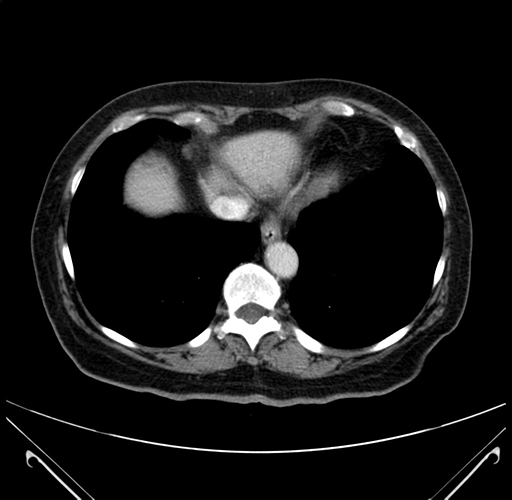

Pre-Chemo: Axial Venous

Axial Venous